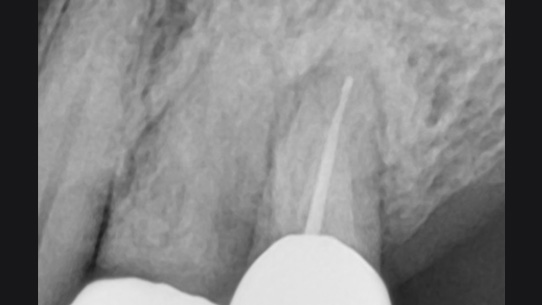

뿌리 주변 염증은 신경관을 소독하고 약재를 삽입하는 신경치료를 시행하였습니다.

신경관 소독

신경관 약재 삽입